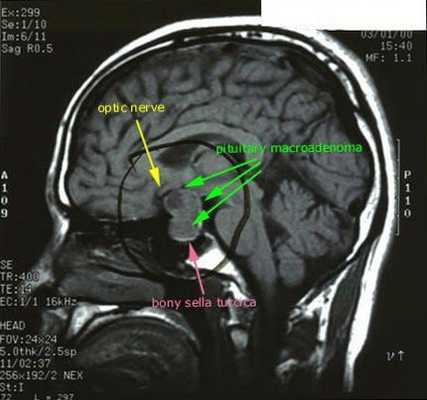

С помощью рентгенографии черепа (турецкого седла) выявляются макроаденомы гипофиза; при КТ и МРТ головного мозга с введением контраста - микроаденомы (в 50-75% случаев). При рентгенографии позвоночника обнаруживаются выраженные признаки остеопороза.

При БИК в 80-85% случаев выявляют микроаденому гипофиза (опухоль до 10 мм), у остальных 15-20% — макроаденому (доброкачественное новообразование от 10 мм). [7]